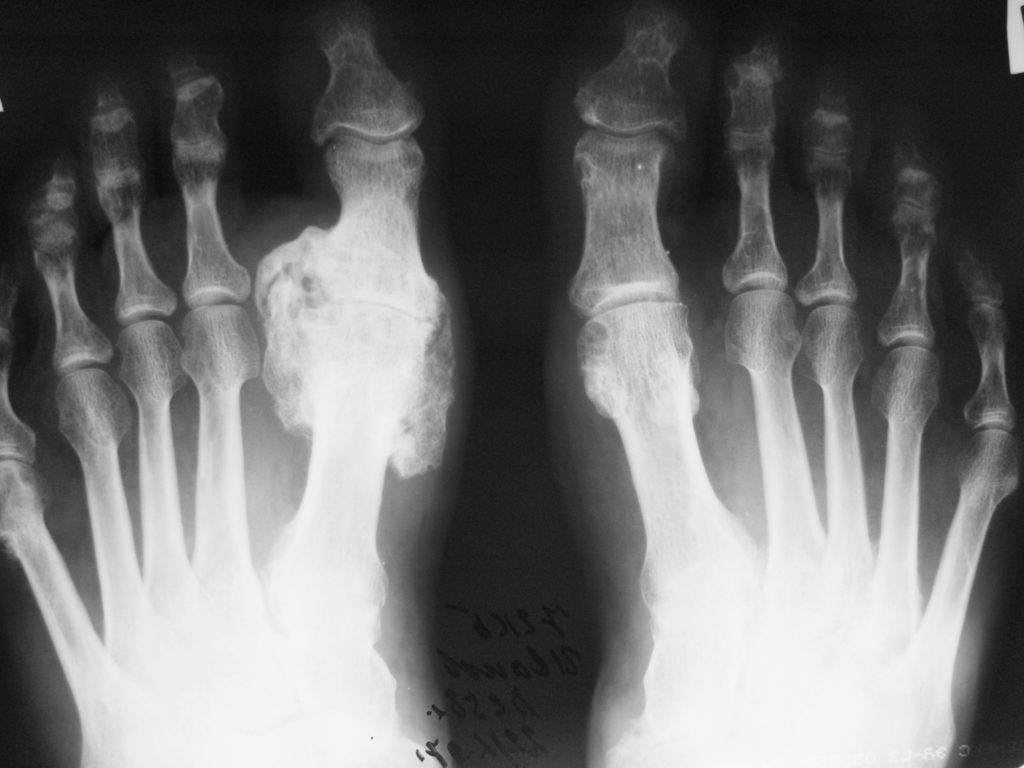

При остром артрите специфические изменения на рентгенограммах не выявляются. Характерные для подагры рентгенологические изменения развиваются обычно не ранее 3-х лет с начала заболевания. При этом одновременно можно наблюдать признаки деструкции, дегенерации и регенерации.

Для подагры типичны внутрикостные кистовидные образования различных размеров, обусловленные тофусами, которые могут располагаться внутри сустава, но, что особенно примечательно, рядом с ним и даже на некотором отдалении. Хронический подагрический артрит может сопровождаться деструкцией хряща (сужение щели сустава) и развитием краевых костных эрозий. Так называемый «симптом пробойника» – краевые костные эрозии или кистовидные образования правильной формы с четкими, иногда склерозированными контурами – наблюдается при подагре нечасто и для нее неспецифичен. Для этого заболевания более характерна возникающая с течением времени выраженная деструкция не только субхондрального участка кости, но и всего эпифиза и даже части диафиза (внутрисуставной остеолиз). При этом могут наблюдаться значительное расширение «изъеденных» суставных отделов костей и заострение их краев. Костные анкилозы при подагре описаны, но наблюдаются чрезвычайно редко (рис. 3).

Всегда своеобразна при подагре локализация рентгенологических изменений. Обычно наиболее выраженная патология обнаруживается в суставах стоп (в первую очередь в суставах больших пальцев) и кистей. Редкой, но известной локализацией рентгенологических изменений при подагре являются плечевые, тазобедренные, крестцово-подвздошные суставы и позвоночник

Важно отметить, что деструктивные изменения суставов или внутрикостные кисты рассматриваются как признак «тофусной» подагры

Костные изменения при подагре редко уменьшаются на фоне специфической терапии, со временем они даже могут несколько увеличиваться. Тофусы, расположенные в мягких тканях, также могут быть обнаружены с помощью рентгенографии, особенно если они кальцифицируются, что отмечается нечасто .